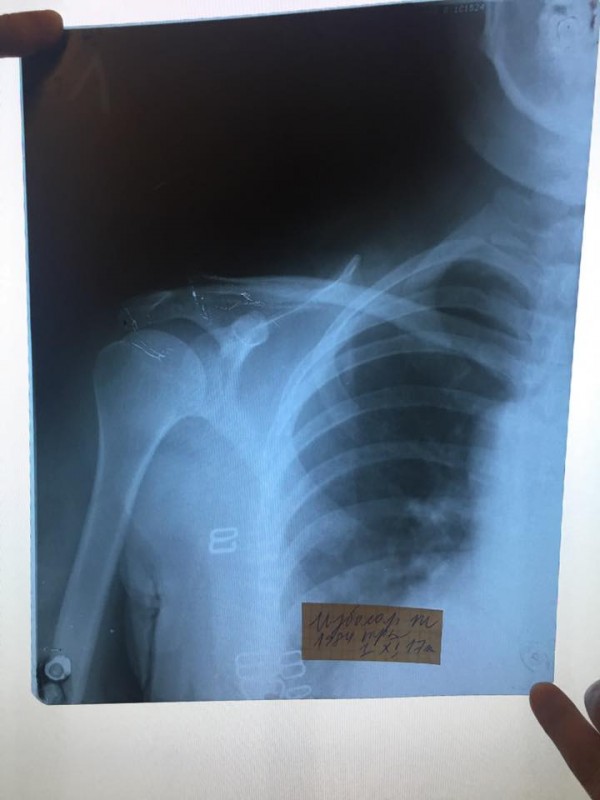

Ночью левая рука стала сильно болеть, обратилась в городскую больницу, рентген показал что у меня закрытый перелом левой ключицы, сейчас я мать четверых детей, гражданка Республики Казахстан стою перед фактом что органы и их сотрудники, которые должны защищать наши права, унизили и растоптали меня, морально и физически уничтожили, сломали мне ключицу, и скорее всего уйдут от ответственности, следователь ДГД сказал мне что решение примется через месяц, это я воспринимаю как "потянуть время", мы простые люди и не имеет высоких покровителей, надежда на общественность, которая может повлиять на этих сотрудников. Такое может произойти с каждым, помогите мне. P.S. на третьем этаже стояли несколько видеокамер, надеюсь записи дойдут до суда!!!", - написала она (пунктуация и орфография в основном сохранены - прим.).

Там же Избасар выложила фотографию заключения травматолога и рентгеновский снимок сломанной ключицы.